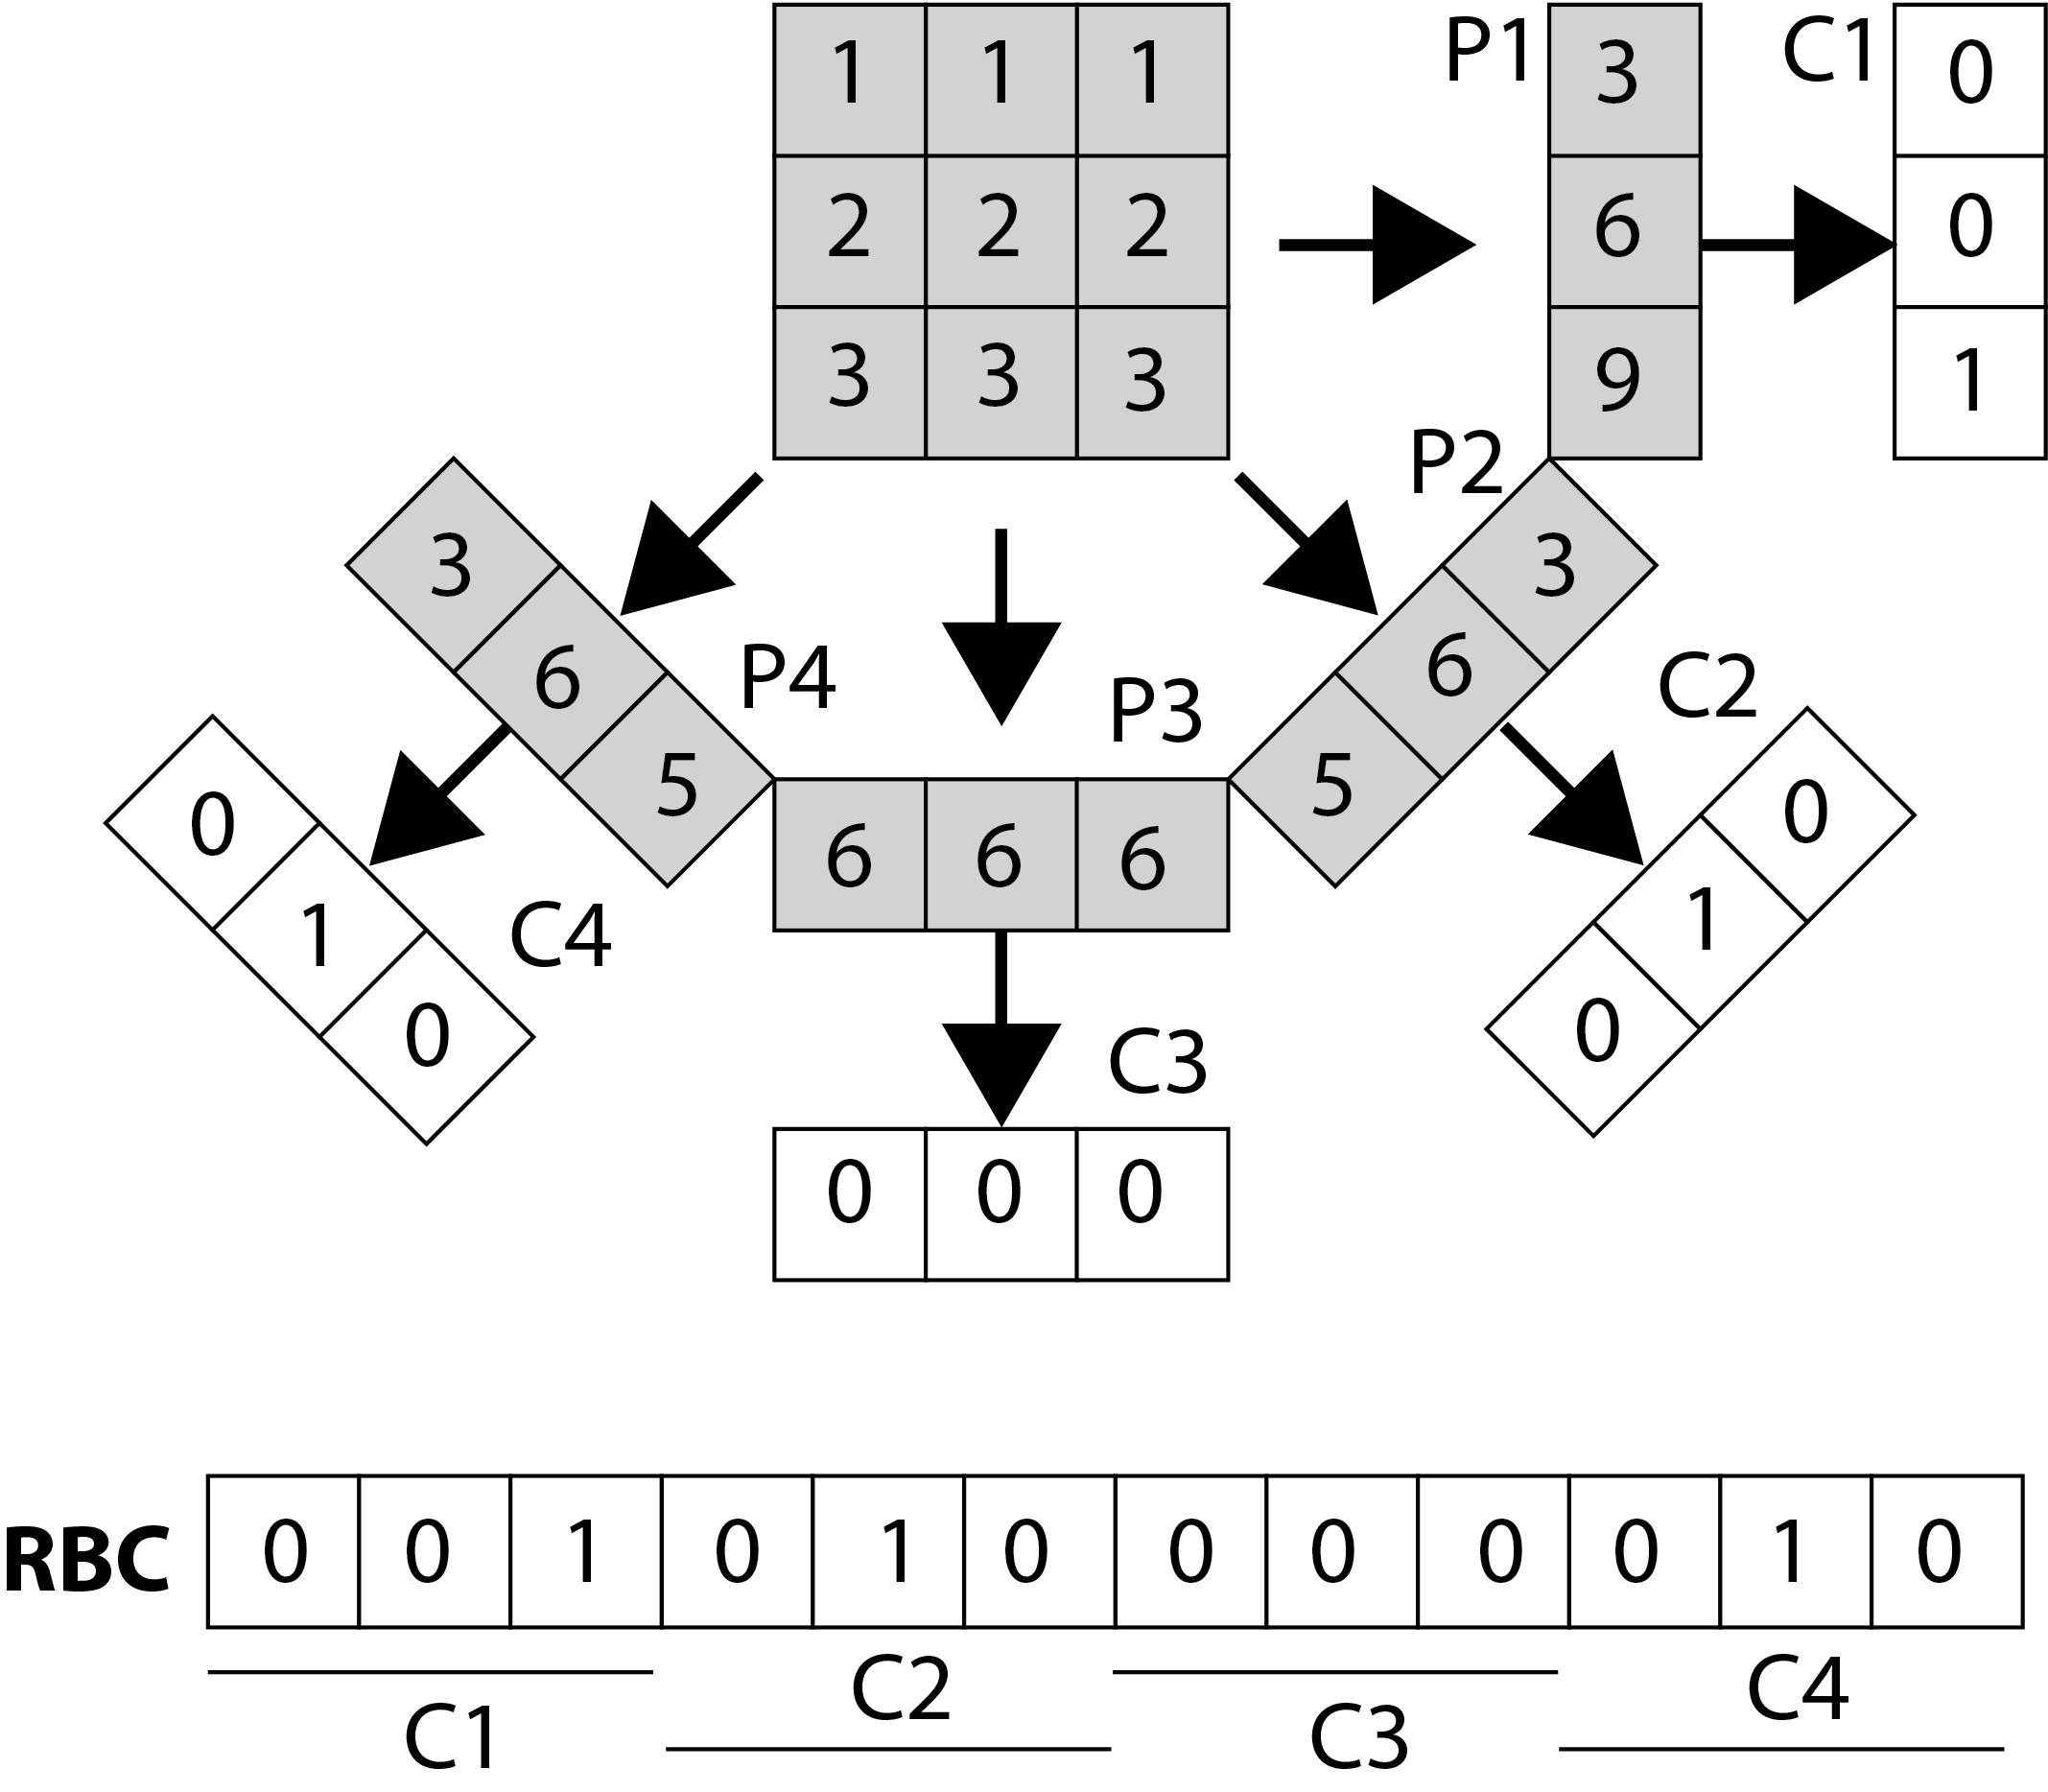

In general, we use the projections to reconstruct the image (if projections are real scans of the physical object). In case of building the Radon transform of an existing image, we can threshold all projections (lines) for individual angles based on a “local” threshold for that angle, such that we can assemble a barcode of all thresholded projections as depicted in Figure 1. A simple way for thresholding the projections is to calculate a typical value via median operator applied on all non-zero values of each projection (zero-padding is common to generate same-lentgh projection vectors for all angles). Algorithm 1 describes how Radon barcodes (RBC) can be calculated111Matlab code available online: http://tizhoosh.uwaterloo.ca/. In order to receive same-length barcodes Normalize downsamples all images into images (i.e., ).

Figure 2 shows barcode annotations for two medical images from IRMA dataset [34, 35] for different values (see lines 4 and 10 in Algorithm 1). Hence, the algorithm works with equidistant angles of projection.